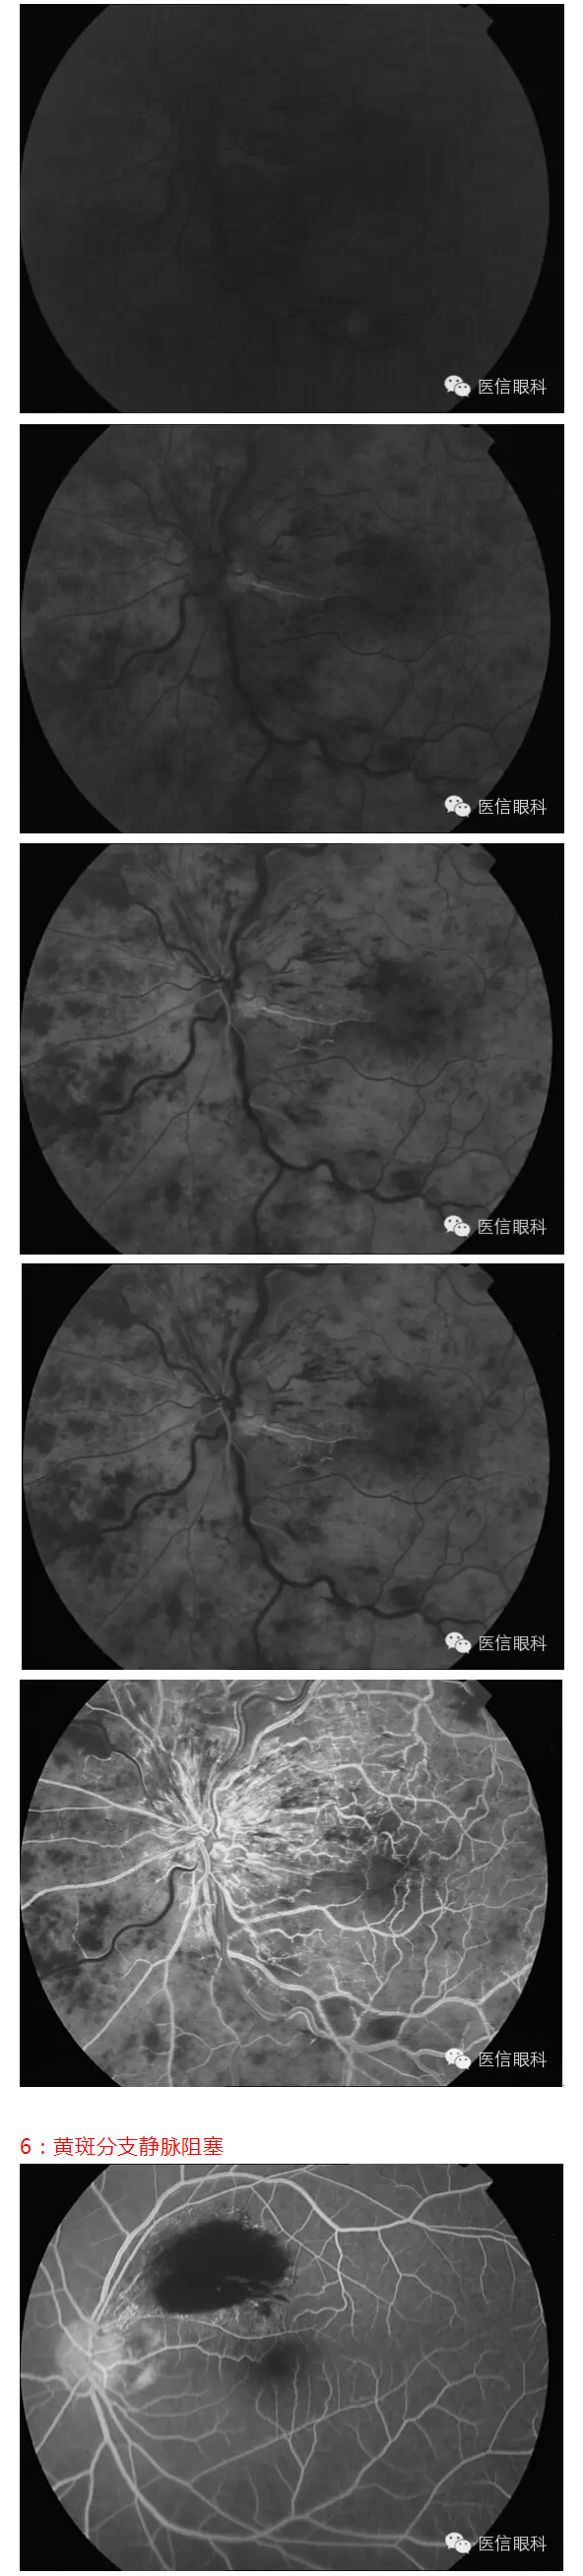

常见眼底病荧光血管造影表现(多图一)